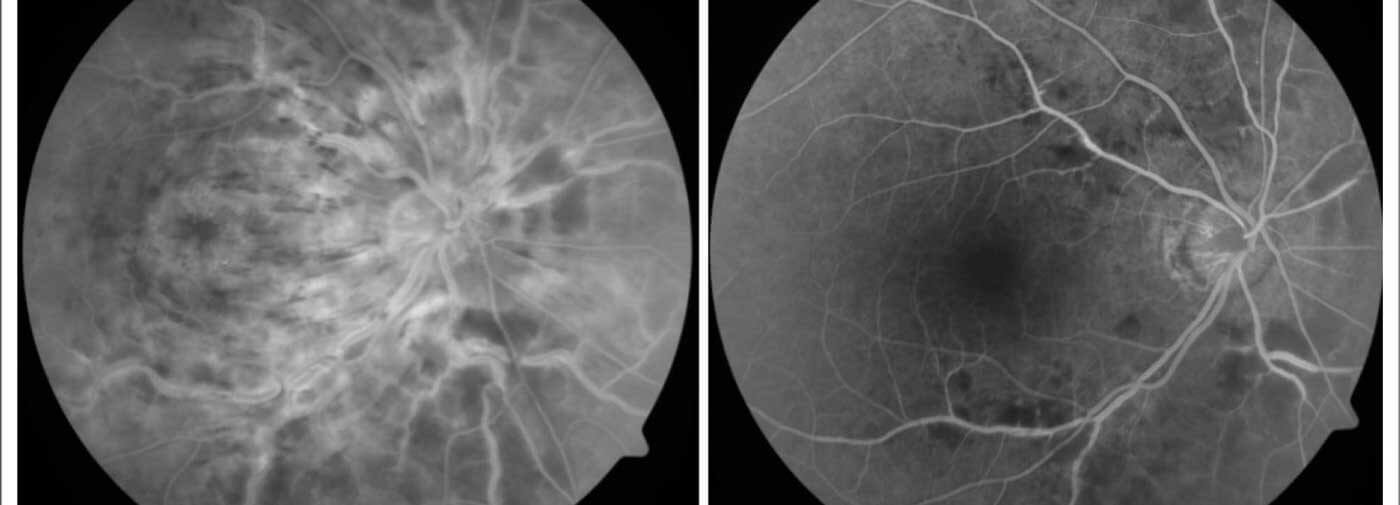

Fundus Fluorescein Angiography (FFA) is a highly specialized diagnostic procedure used to visualize the blood vessels in the retina and choroid layers of the eye. It involves injecting a fluorescent dye called fluorescein into a vein, typically in your arm or hand. This dye circulates through the bloodstream and highlights the retinal vessels under a special camera that captures detailed images, helping eye specialists detect abnormalities such as blood vessel leakage, blockages, or new vessel growth.

As the dye reaches the retinal vessels, a special fundus camera takes rapid sequence photographs.

The images show the circulation of blood through the retina and can identify leaking vessels, blockages, or abnormal growth.